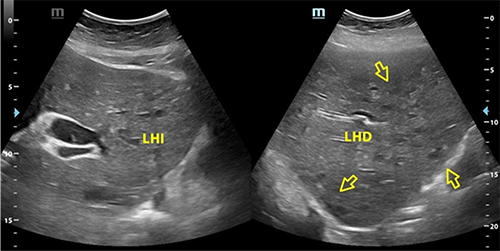

Dentro la evolución del cuadro clínico la paciente presentó una evolución estacionaria, persistiendo con taquicardia, y taquipnea, además de leucocitosis de 19 200 con neutrofolia de 95%, a pesar de haber removido la causa de la obstrucción (coledocolitiasis) y haberse administrado antibióticos (ceftriaxona 1 g EV cada 12 horas y metronidazol 500 mg EV cada 8 horas) durante 72 horas. Es así, que se realiza nueva ecografía abdominal (Figura 2) la cual reportó: “microabscesos hepaticos?, dilatación de vía biliar extrahepática hasta 18 mm y vesícula con barro biliar”, por lo que tras ser valorada por el servicio de medicina interna se decide realizar tomografía axial computarizada (TAC) de abdomen con contraste y en el contexto de una sepsis de foco abdominal por probables microabscesos hepáticos se decide rotar el esquema de tratamiento antibiótico a meropenem 1 g EV cada 8 horas, descontinuando ceftriaxona, y continuando metronidazol 500 mg EV cada 8 horas. En misma fecha se realiza TAC de abdomen con contraste (Figura 3 y 4) la cual reporta: “hepatomegalia, innumerables microabscesos hepáticos, dilatación de vía biliar intra y extrahepatica, a descartar engrosamiento de la pared lateral izquierda de la vesícula biliar, ganglios periportales de etiología por determinar (origen inflamatorio vs metastásico) y mínimo derrame pleural bilateral”. Posteriormente, se solicitan marcadores tumorales de CA 19.9, CA 125, AFP y CEA, todos ellos con resultados dentro de parámetros normales.